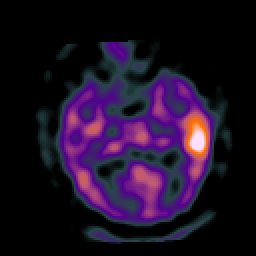

Subacute Stroke, overlay -- Slice #11

[Home][Help][Clinical] Slice 11